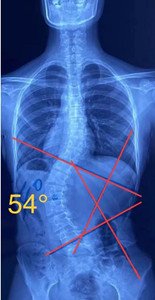

單向側(cè)彎

如果是單向側(cè)彎的患者,(腰彎或者胸彎),躺在床上,應(yīng)向患側(cè)處進(jìn)行臥位,側(cè)臥在你彎弧的凹側(cè),讓它下墜打開。